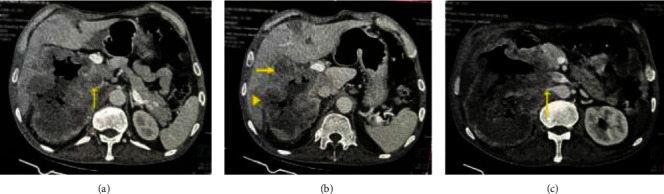

急性上消化道出血(UGIB)是一种医疗急症,最常见的病因是消化性溃疡病(PUD)或静脉曲张出血。然而,通过侵犯小肠引起 UGIB 的癌症并不常见,而肾细胞癌(RCC)侵犯十二指肠的情况更是罕见。一名 55 岁的男性患者出现血便和右侧腹痛。食管胃十二指肠镜检查(EGD)发现十二指肠内有活动性出血源,后经造影剂增强计算机断层扫描(CECT)确定为 RCC 直接延伸引起的十二指肠瘘(DRF)。影像学检查证实存在浸润邻近器官的恶性肾肿块。这种RCC伴有DRF并表现为UGIB的非典型表现强调了对消化道出血病例进行全面评估以确定罕见潜在病因的重要性。

Acute upper gastrointestinal bleeding (UGIB) is a medical emergency with most common cause being peptic ulcer disease (PUD) or variceal bleeding. However, cancers that cause UGIB by invading the small intestine are uncommon, and the invasion of renal cell carcinoma (RCC) into the duodenum is an even rarer occurrence. A 55-year-old male presented with melena and right flank pain. Esophagogastroduodenoscopy (EGD) revealed an active bleeding source in the duodenum, later identified on contrast-enhanced computed tomography (CECT) as a duodenorenal fistula (DRF) caused by direct extension of the RCC. The imaging confirmed the presence of a malignant renal mass infiltrating adjacent organs. This atypical presentation of RCC with DRF manifesting as UGIB underscores the importance of comprehensive evaluations in cases of gastrointestinal bleeding to identify rare underlying causes.